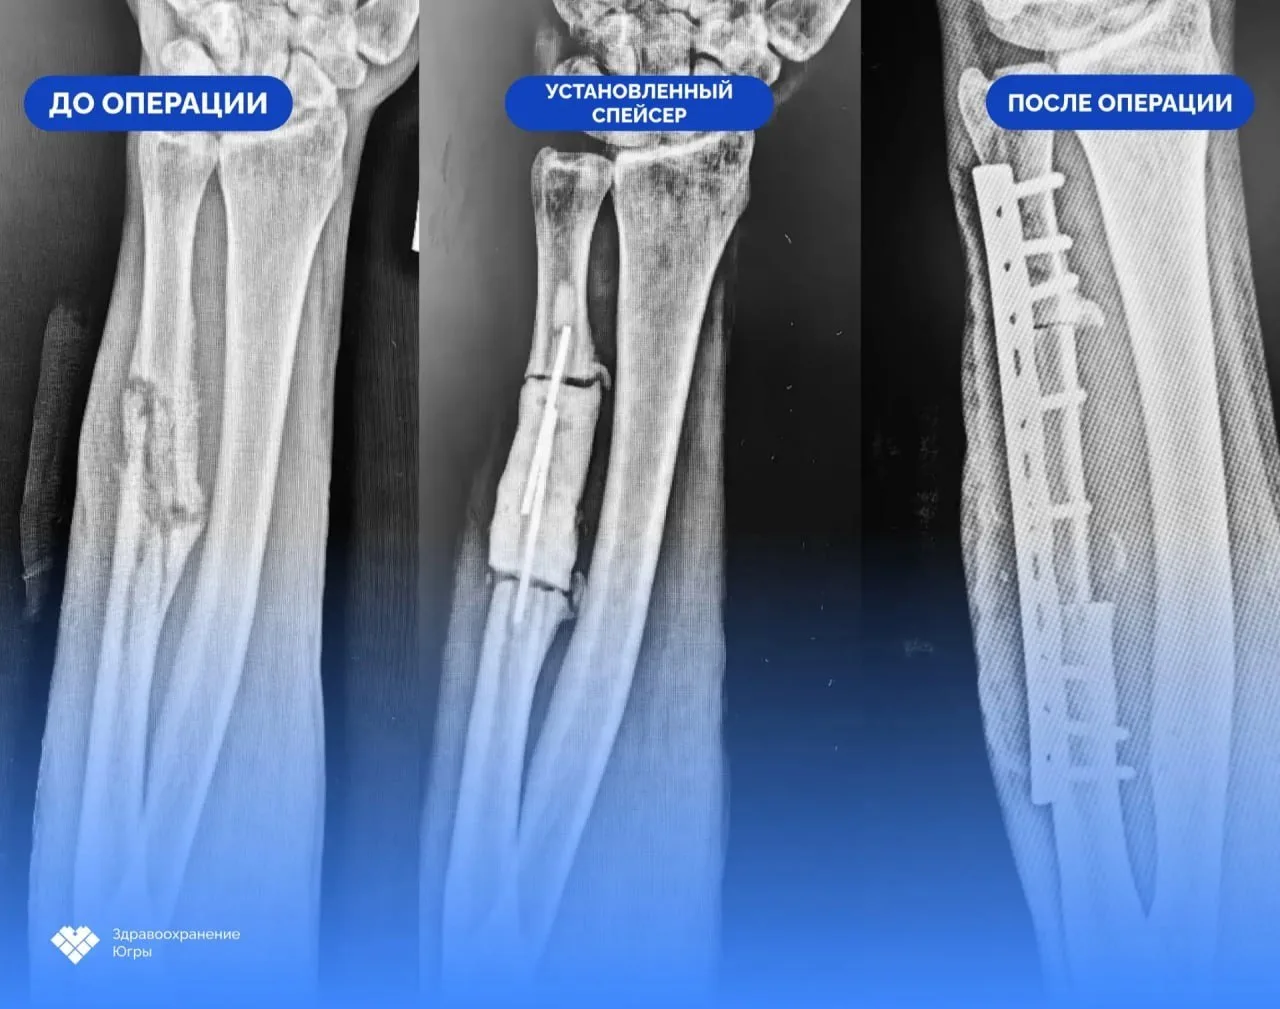

Врачи дважды его оперировали: сначала удалили омертвевшую ткань и очаг инфекции, затем наложили антибактериальный спейсер — временный цементный эндопротез с добавлением антибиотика.

«При повторной госпитализации пациента контрольные исследования показали, что воспалительный процесс купирован. Травматологи-ортопеды удалили спейсер и приступили ко второму этапу лечения – костной пластике.

С применением микрохирургической техники врачи выделили фрагмент малоберцовой кости вместе с сосудистым пучком и пересадили его в зону дефекта. Сосудистый компонент трансплантата был совмещен с локтевой артерией и получил местное кровоснабжение»,